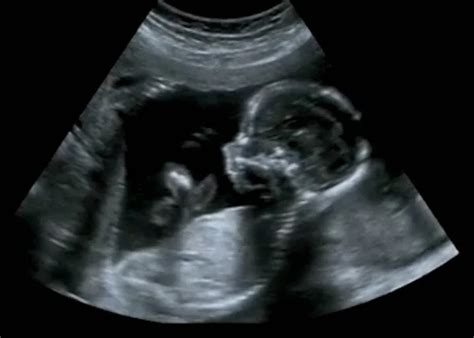

Az ultrahangos vizsgálat során az orvos egy sötét foltot lát a méhben, amely a petezsák, de hiányzik belőle a szikhólyag vagy az embriócsomó. Ez a diagnózis általában a 6. és 7. terhességi hét környékén válik biztossá, amikor már látszódnia kellene a szívműködésnek.

A hüvelyi ultrahang vizsgálat pontosabb, megbízhatóbb, mint a hasi. Az első vizsgálat a terhesség alatt hüvelyi ultrahanggal történik. A várandósság első 12 hetében szinte mindig ezt használják. Ez nem fájdalmas a kismamának és egyáltalán nem jelent semmilyen veszélyt a picire. Egy hosszúkás, kis gömbben végződő vizsgálófejre gumi óvszert helyeznek, majd speciális zselét tesznek rá és óvatosan bevezetik a hüvelybe.

Az 5. hét végén a petezsák jelenik meg, ezt keresik a méhben, mert ez lesz a kis embriócsomó otthona. Az ultrahang képen ez egy jól körülhatárolt kis fekete folt lesz a szürkés színű háttérben. Megállapítják, hogy jó helyen található-e, nincs-e méhen kívüli terhesség. A petezsákban nagyjából a 6. hétben láthatóvá válik a szikhólyag, ami a kis embrió táplálásáért felelős, amíg a méhlepény át nem veszi a szerepét. Önmagában azonban sem a petezsák, sem a szikhólyag jelenléte még nem garantálja, hogy van-e, lesz-e benne embrió. A terhesség tényét akkor állapítják meg, amikor már az embriócsomó is látható a szikhólyagban és a szívkezdeménye dobog. Ez általában a 6-7. terhességi hét környékén, de késői peteérés esetén nem ritkán csak a 8. héten történik meg.

A diagnózist általában akkor mondják ki, ha a petezsák eléri a 25 mm-es átmérőt, de nem látható benne embrió, vagy ha két, legalább egy hét különbséggel elvégzett ultrahangvizsgálat sem mutat fejlődést.